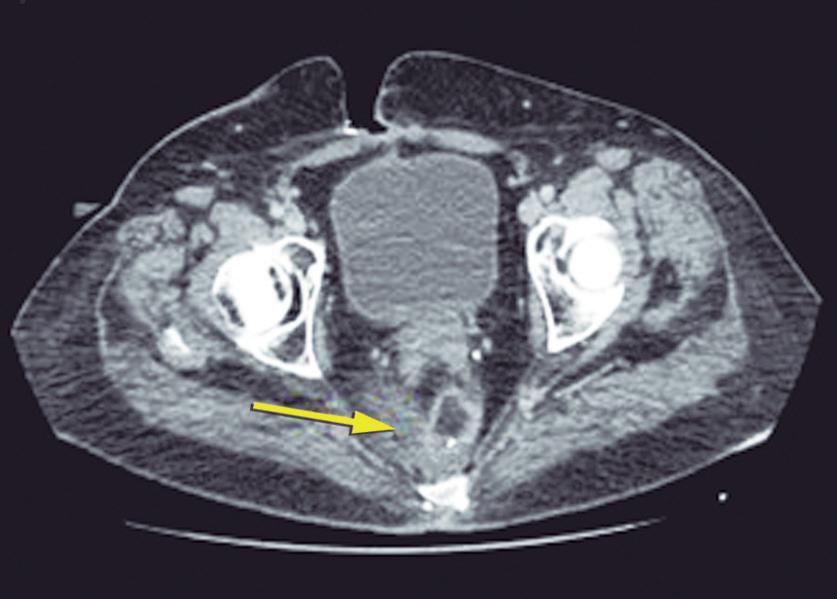

El absceso anal se presenta como un cuadro anal doloroso de desarrollo progresivo, y la intensidad del dolor se acrecienta en el transcurso de unos pocos días.11 (Figura 11)

Figura 11. Absceso anal posterior con abultamiento fluctuante de la piel tenso y doloroso

El mismo puede asociarse a algunos síntomas sistémicos como fiebre, malestar general y leucocitosis. En el examen físico se presenta como un tumor con eritema cutáneo, con aumento de la temperatura. Presenta tensión, puede fluctuar y produce intenso dolor durante la palpación. En el caso de los abscesos interesfintéricos el dolor puede ser muy intenso, pero no evidenciarse el absceso durante la inspección anal o palpación. Habitualmente, el dolor hace imposible la realización del tacto rectal.11 En los casos de sospecha diagnóstica o de requerir un estudio topográfico del absceso la realización de una tomografía con contraste o una resonancia ayuda en el diagnóstico y puede guiar la elección de la vía de drenaje.19 El tratamiento del absceso es quirúrgico con la realización de un drenaje transcuatáneo o transrectal.20 Es conveniente aclarar al paciente que es posible que durante la cicatrización se desarrolle una fístula anal. Esto ocurre en más de la mitad de los pacientes, más frecuentemente en las mujeres con fístulas anteriores.21